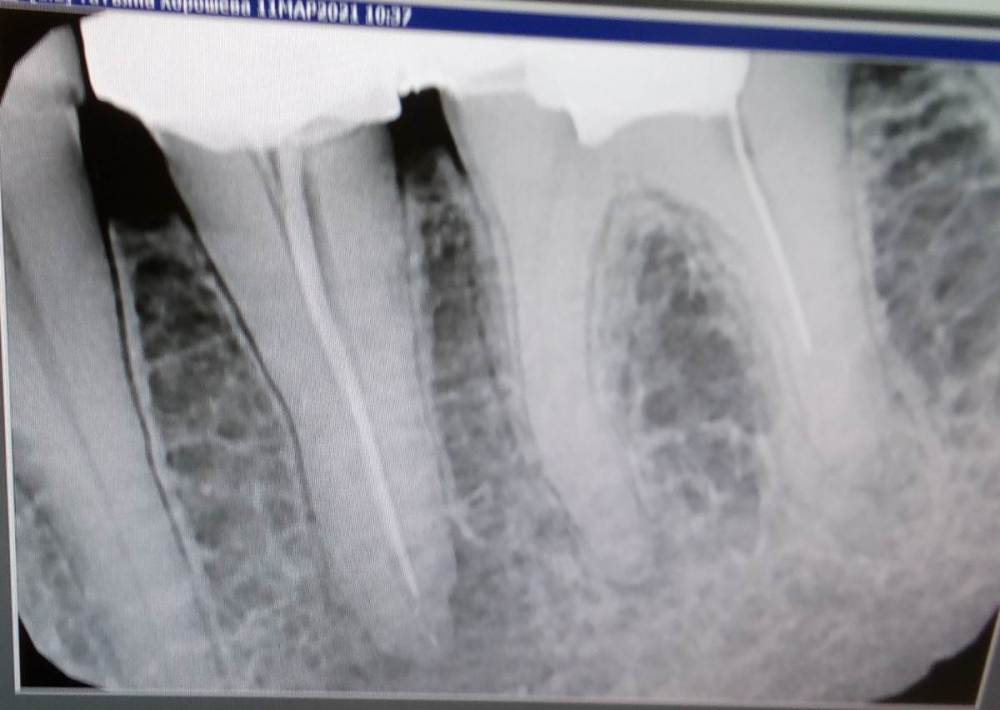

Татьяна-spb Опубликовано 30 июля, 2021 Поделиться Опубликовано 30 июля, 2021 Добрый день! Зуб перелечен около 6 лет назад, установлена коронка, в марте этого года был флюс, сделали послабляющий надрез, назначили антибиотики.По мнению дежурного врача поликлиники канал запломбирован плохо,киста большая, зуб однозначно под удаление, со слов стоматолога частного-можно попробовать перелечить под микроскопом, но шансы на благоприятный исход не более 20%( т.к. в канале есть обломок инструмента). Стоит ли пробовать перелечивать? Ссылка на комментарий

It'sGeorgy Опубликовано 30 июля, 2021 Поделиться Опубликовано 30 июля, 2021 (изменено) Добрый день! 51 минуту назад, Татьяна-spb сказал: киста большая Размер «кисты» не влияет на успешность перелечивания. Я за перелечивание и пятого, и шестого зуба. Но, надо понимать, что это безгарантийная работа. Изменено 30 июля, 2021 пользователем It'sGeorgy Ссылка на комментарий

St. Опубликовано 30 июля, 2021 Поделиться Опубликовано 30 июля, 2021 Добрый день. Я тоже за перелечивание. Шанс на успех довольно высокий. Показаний к удалению не увидела. Ссылка на комментарий